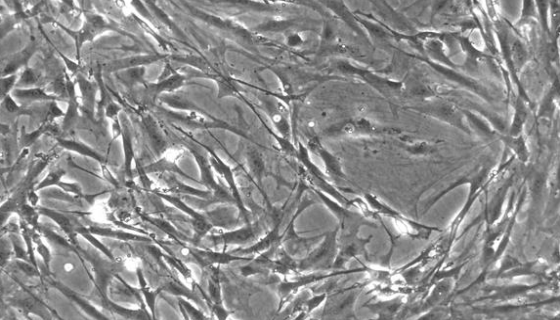

大鼠骨髓间充质干细胞的传代方法及应用!

大鼠骨髓间充质干细胞是从成年大鼠骨髓组织中分离得到的,原代冻...